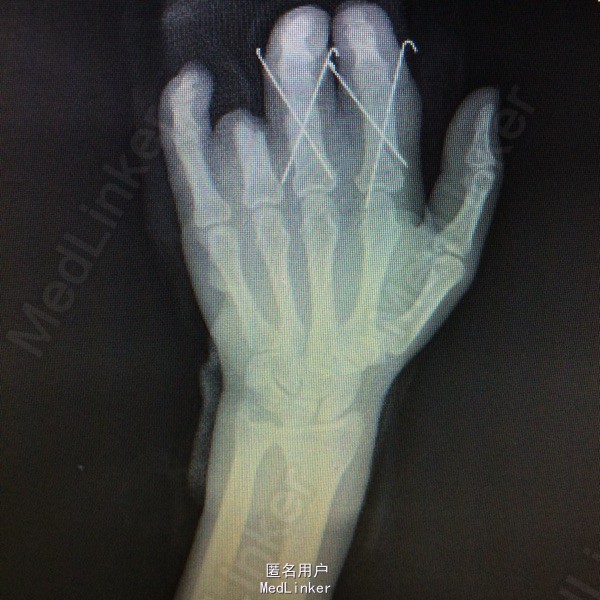

初步诊断:左手2-5指压伤不全离断 治疗计划:1、完善相关检查及术前准备:心电图,血常规,尿常规,肝肾功能电解质、术前全套等。 2、臂丛麻醉下行再植术。 3、术后“三抗”治疗,烤灯保暖。再植术 左手2-4指骨折复位交叉克氏针固定,

左手2-4指骨折复位交叉克氏针固定,透视检查骨折复位固定良好;患者诉伤口轻度疼痛,无发热症状。查体:伤口无异常分泌物,手指血供良好,手指屈伸受限。主任医师查房查房看过病人,患者术后第10天,拟明日出院,嘱定期伤口换药,门诊随诊。 请问各位专家,术后多久康复锻炼效果最好,?怎么预防坏死?